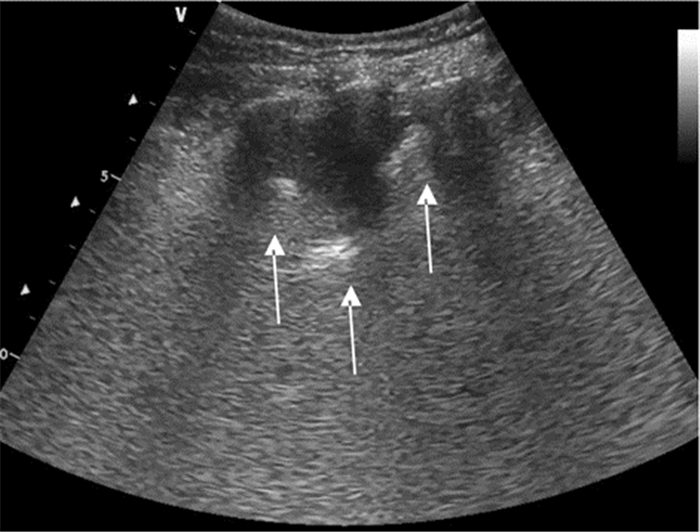

将探头置于目标肋间隙,于胸壁软组织下可见一条随呼吸滑动的高回声线,即为胸膜线,其后可见与之平行、等距、回声强度不断衰减的多条线——A线(图 8)。胸膜线随呼吸往复运动的图像称为“肺滑动”,M型超声表现为肋骨下方0.5 cm随呼吸向探头方向往复运动的高回声线,即“沙滩征”。部分正常人膈肌上方最后一肋间隙可探及少于3条发自胸膜线、垂直延伸至屏幕边缘而不发生衰减、随呼吸往复运动的激光束样图像——B线(图 9)。

| 图 8 正常肺部超声征象:左图横向箭头所示为A线,其与胸膜平行等间距逐渐减弱。右图为M超下“沙滩征” |